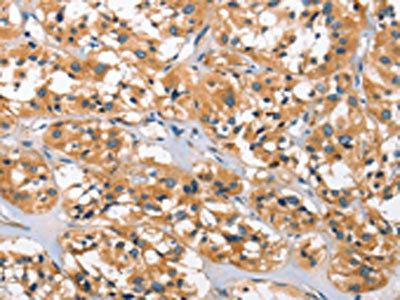

The image on the left is immunohistochemistry of paraffin-embedded Human thyroid cancer tissue using CSB-PA274333(DKK3 Antibody) at dilution 1/30, on the right is treated with fusion protein. (Original magnification: ×200)